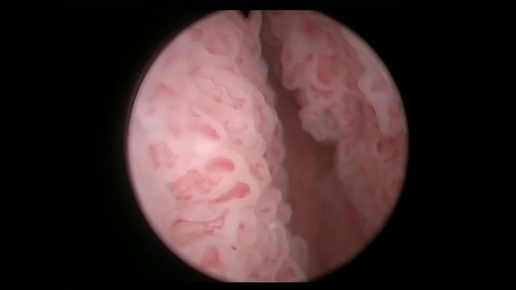

Цистоскопия. Тотальное поражение мочевого пузыря опухолевым процессом.

Денис Давыдов врач-уролог, онкоуролог